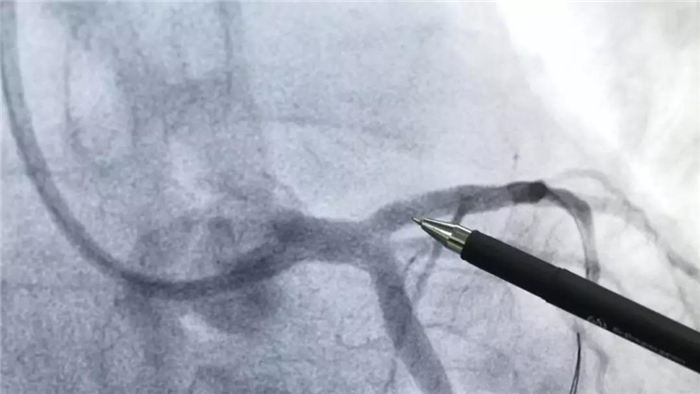

血运重建手术后

手术中,心血管病介入团队将患者的血栓抽出,植入支架,再经心血管内超声(IVUS)检查显示:患者支架贴壁良好,无夹层、血肿、血栓影,前向血流TIMI3级。经过45分钟,手术顺利完成,患者胸痛、胸闷症状消失,安全返回病房,患者及家属均对这次手术给予了肯定。